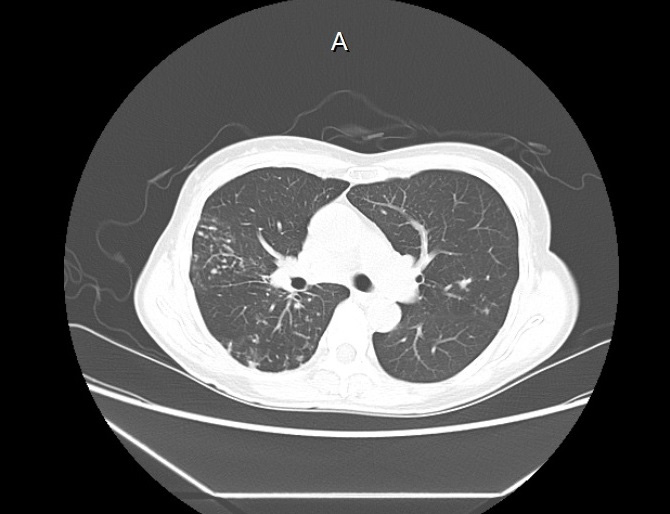

기관지확장증의 CT 사진

​기관지벽의 근육 및 탄력 성분의 파괴로 인해 기관지가 비정상적으로 늘어나 여러가지 문제를 일으키는 질환을 말합니다.

확장된 기관지 내부에는 가래가 고이게 되는데 기관지가 손상되어 있는 상황이므로 잘 빠져나가지 못하게 되고 이로 인해 쉽게 감염되고 그러면서 기관지 벽이 약해집니다. 이렇게 되면 기관지가 쉽게 파괴되고 다시 가래가 증가되는 악순환이 형성됩니다.